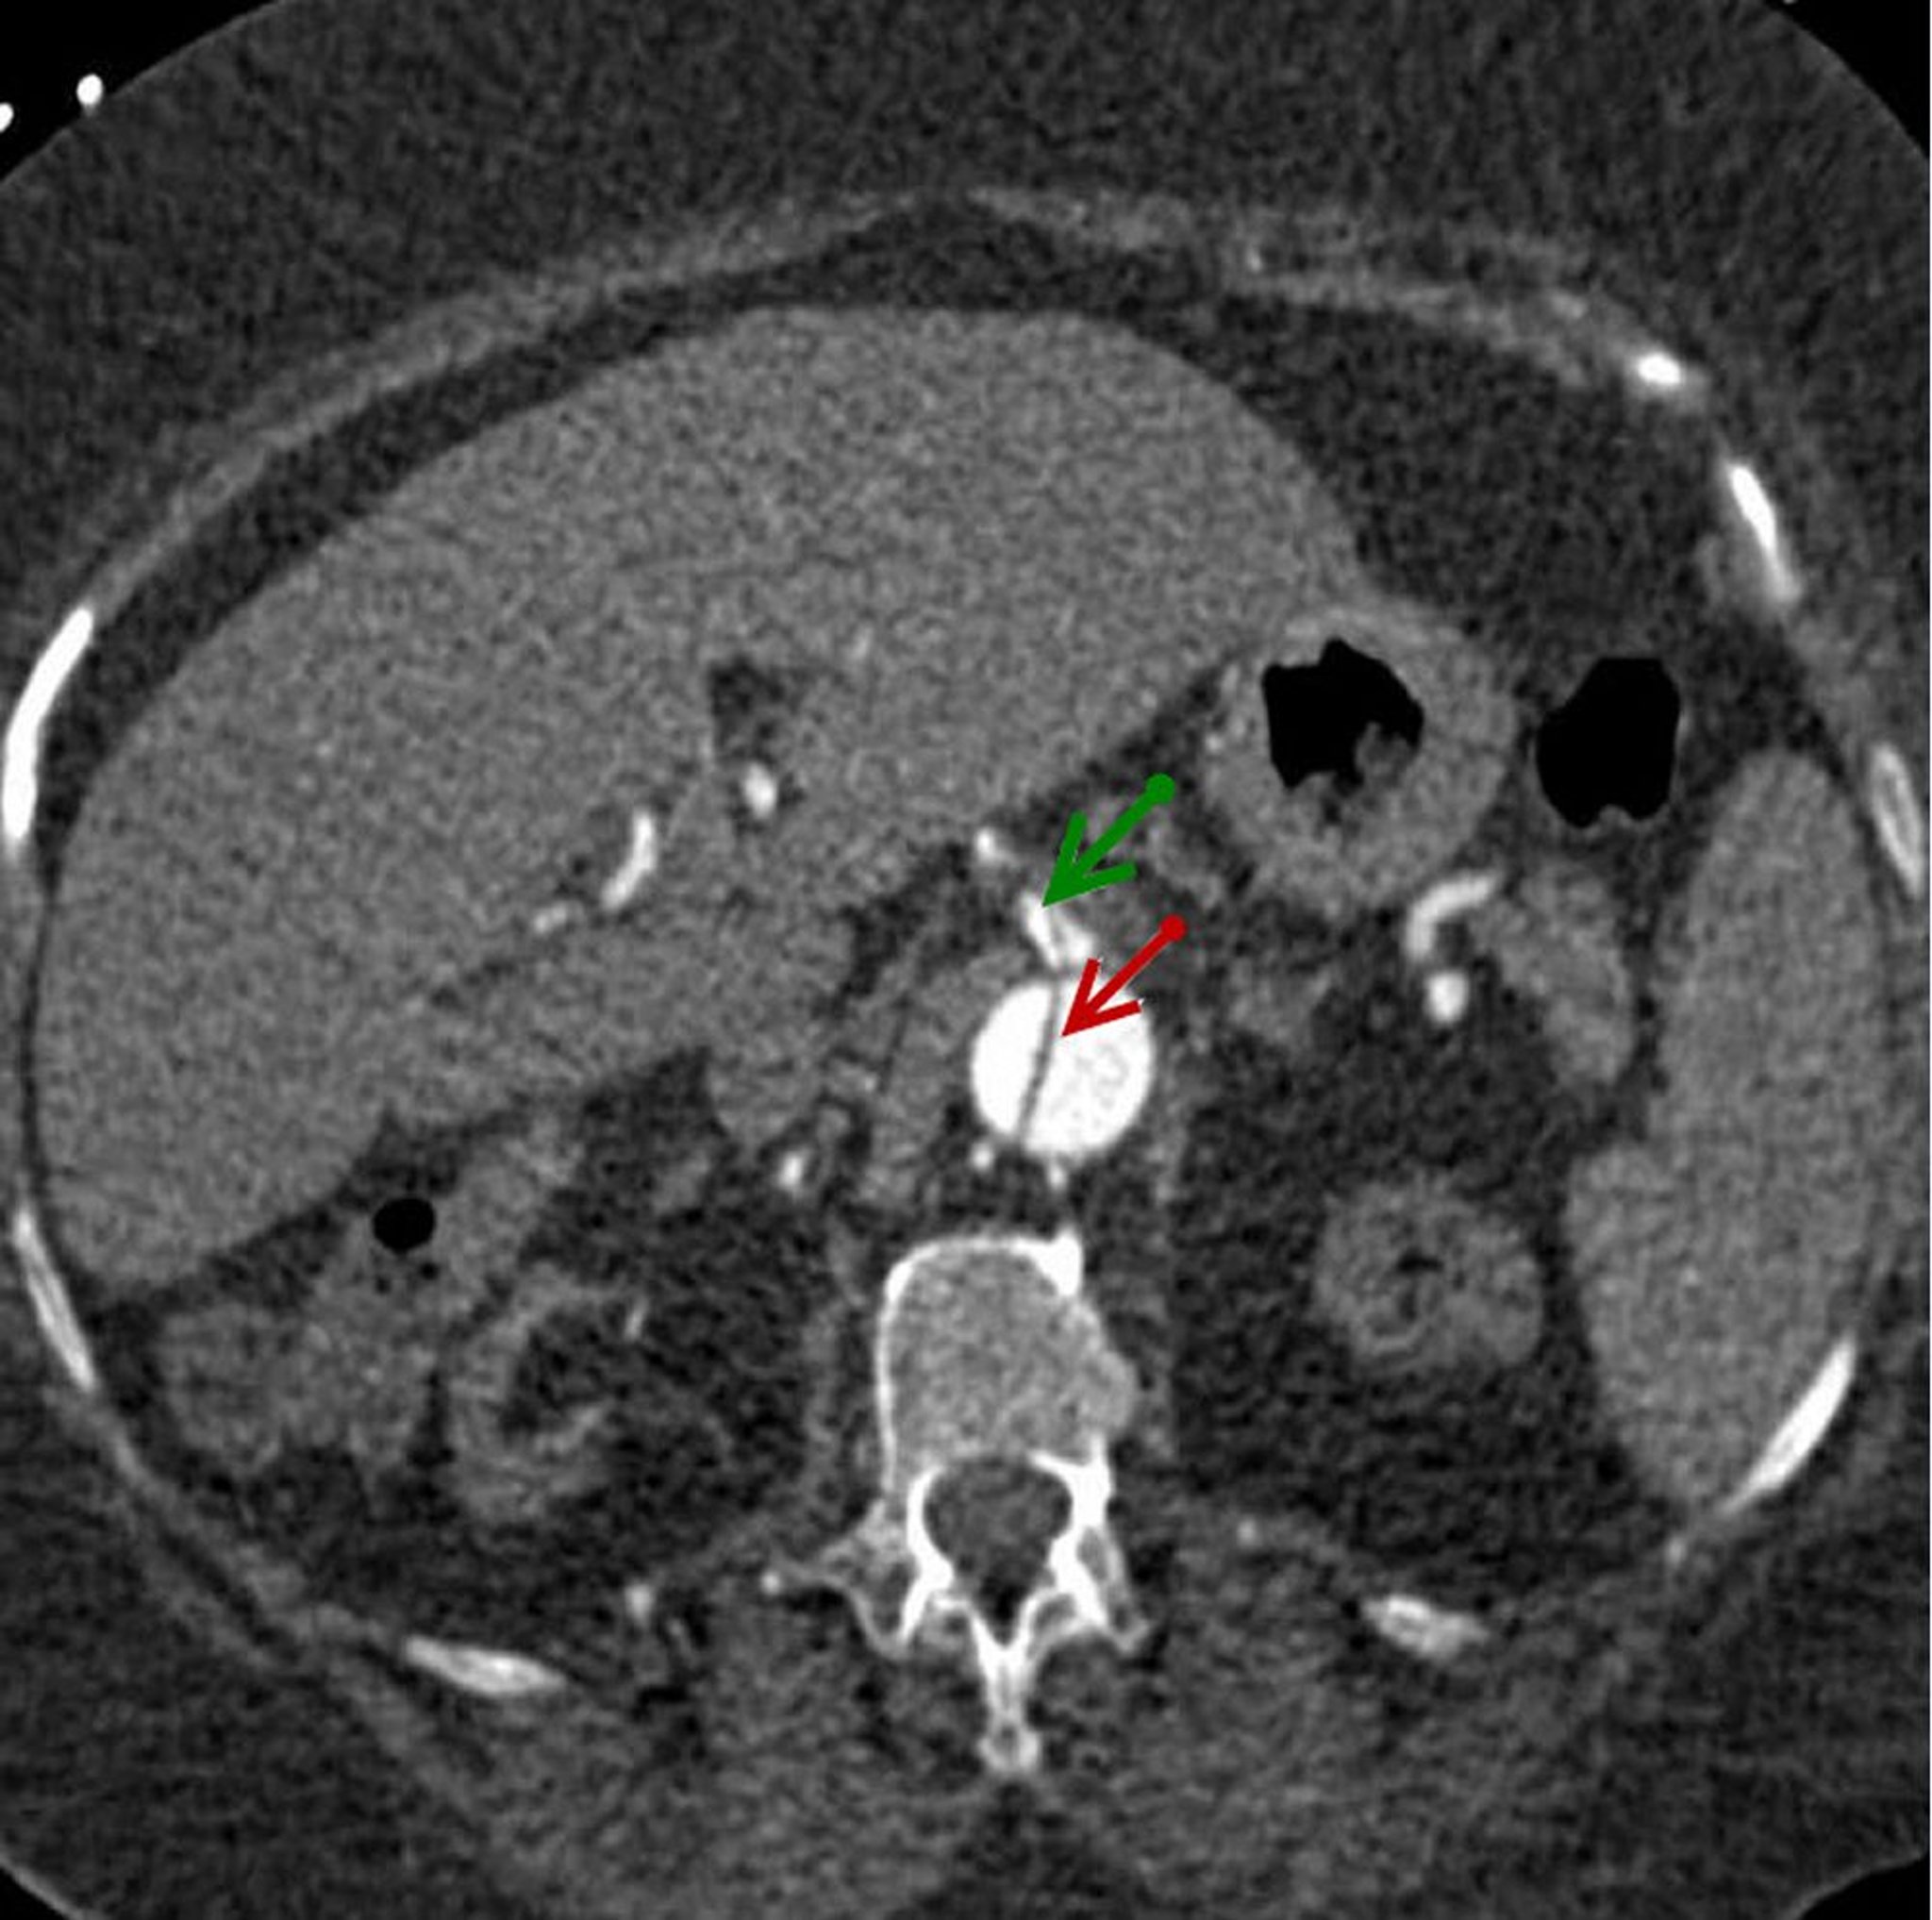

Осевое изображение диссекционного лоскута в нисходящей брюшной аорте (красная стрелка), распространяющегося на верхнюю брыжеечную артерию (зеленая стрелка).